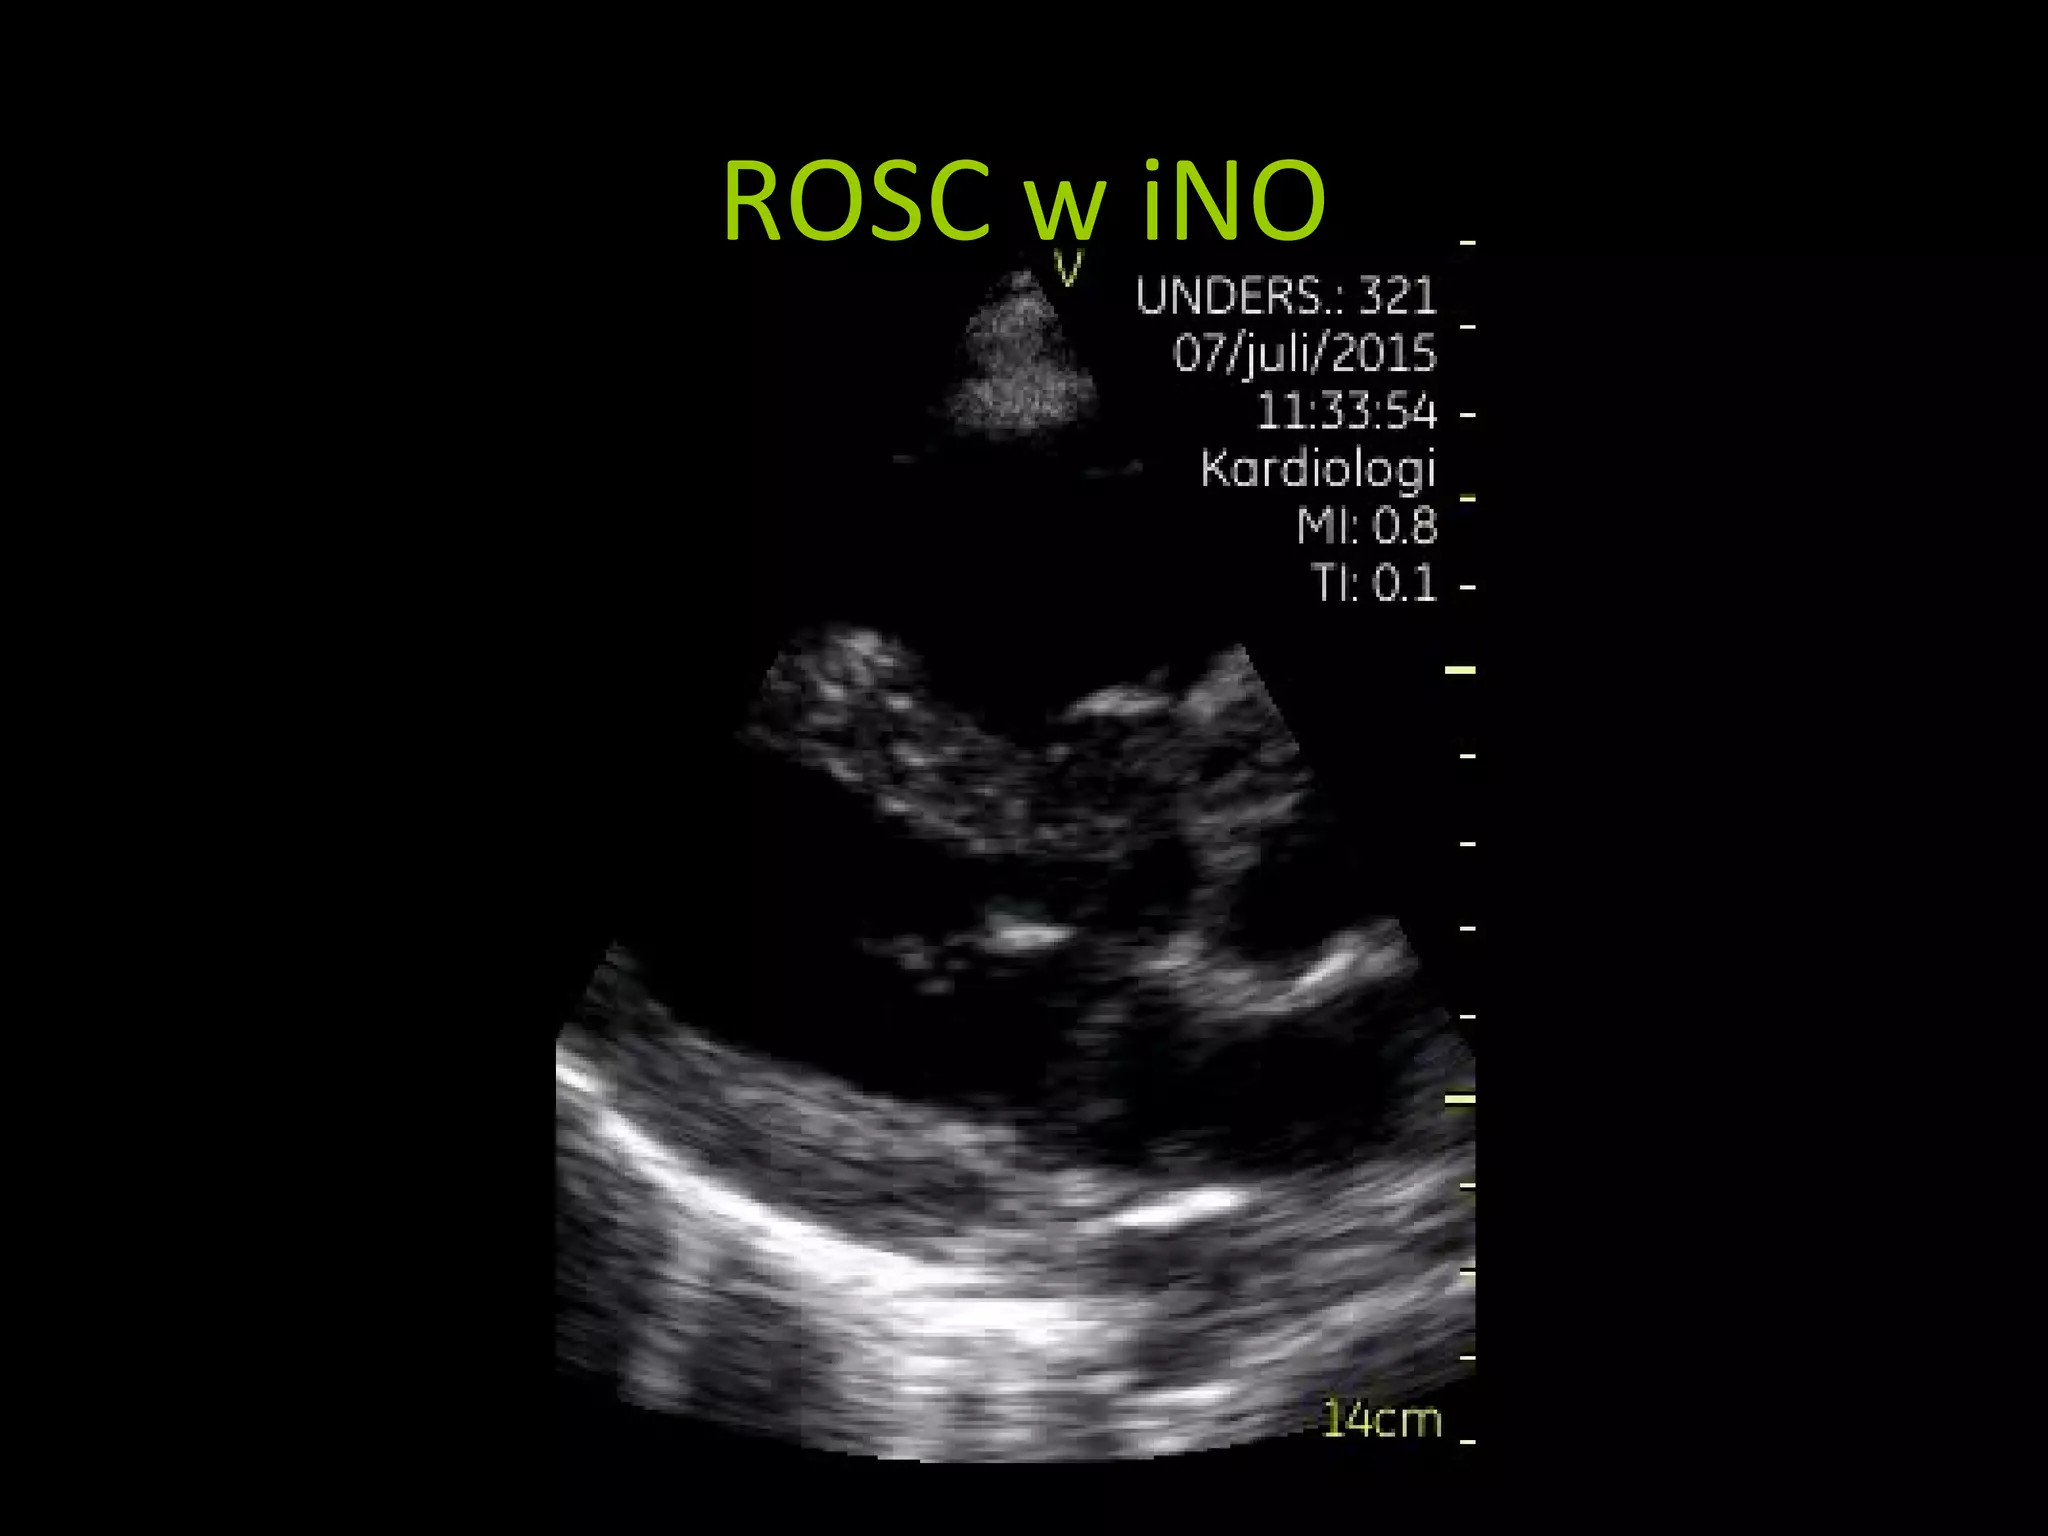

ROSC w iNO

Retrieved in helicopter to

University Hospital

iNO treatment

Reduce vasopressors

Survivor